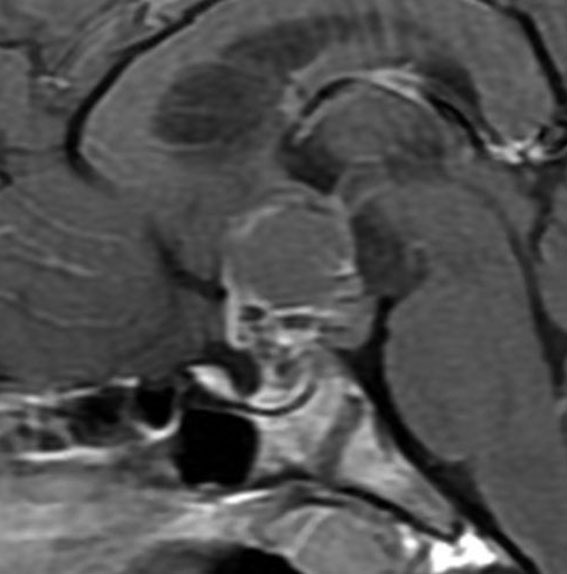

この子の症状は頭痛だけ。両親はなぜ気づかなかったのかと疑問を持ちますが,巨大になるまで症状が出ないこともあるのです。左のCTで腫瘍の周囲にバラバラと白い点状の石灰化があるので診断できます。左の視床下部から発生したクラニオでした。開頭手術しますが超高難易度です,怖いです (┯_┯) 複数回開頭手術になりましたが結果的に全摘出できています (by Dr 山本哲哉)。

ちょっと大きな頭蓋咽頭腫です

嚢胞(液体が入っている袋)の部分と,腫瘍細胞が固まっている実質部分が入り交じっています。このくらいの大きさになってしまうと,下垂体機能を残すことはとても難しくなります。視神経が圧迫されて視力低下と視野障害を生じます。第3脳室が腫瘍で閉塞していて水頭症になっていますから知能の活動が低下します。

腫瘍を摘出するのに危ないのは,脳の血管の損傷です。左では白く,右では黒く線状に移っているのが太い脳動脈です。これら以外にもたくさんの細い重要な動脈が絡んでいます。

幸いこの患者さんの腫瘍は摘出できて患者さんは元気になりました。でもこのくらいのサイズになると手術がいつもうまくいくとは限りませんし重大な障害が残ることもあります。